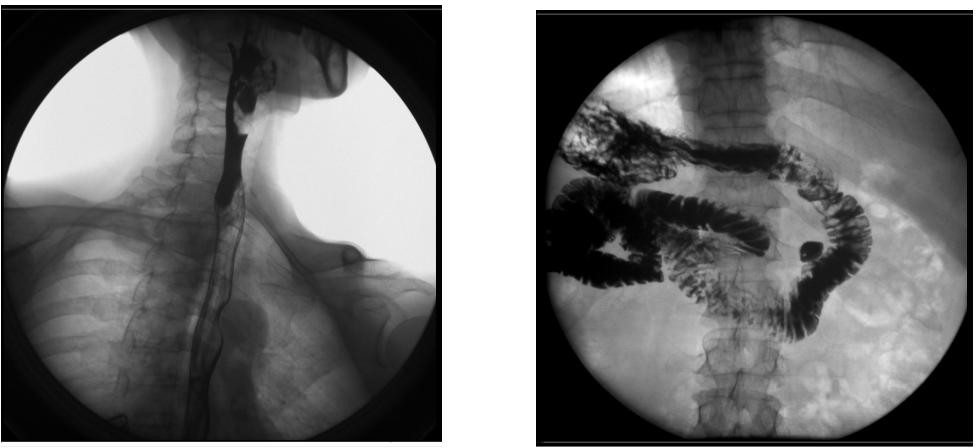

【臨床圖像】

1) 胃腸數(shù)字化透視、消化道造影檢查,胸部、頭顱及全身骨骼普通攝影。

2) 胃腸、食道、脊髓、關(guān)節(jié)腔、膽道、支氣管、靜脈、周邊血管、泌尿系統(tǒng)、子宮輸卵管等數(shù)字化造影。